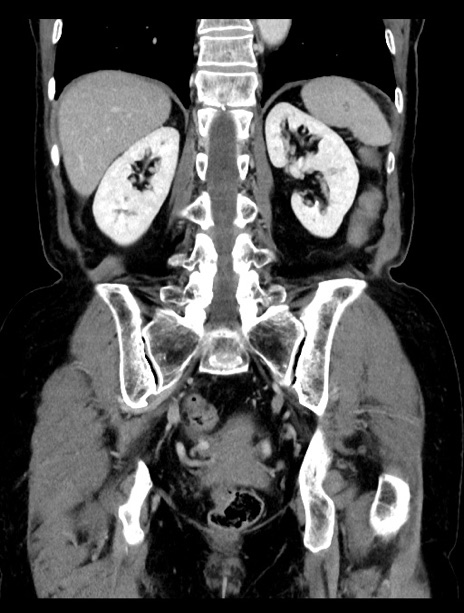

症例23(冠状断像)

【症例】70歳代女性

【主訴】下腹部痛・嘔吐

【現病歴】2日前より腹痛あり。昨日嘔吐あり。症状改善しないため来院。

【既往歴】胃GISTに対して胃部分切除後。

【身体所見】BT 37.1℃、BP 128/77mmHg、腹部:平坦・軟、下腹部に圧痛あり。

【データ】WBC 10200、CRP 0.31